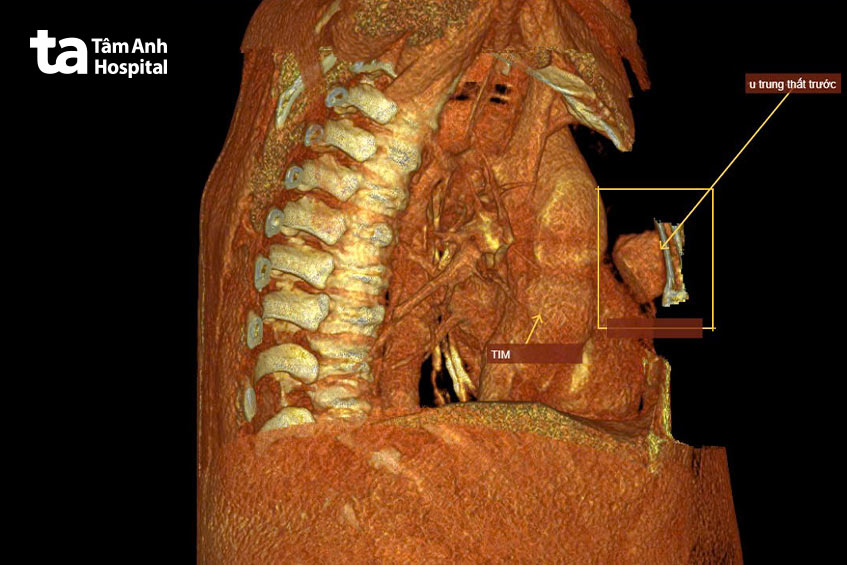

Ngày 6/2, qua thăm khám lâm sàng, BS.CKI Trần Quốc Hoài, khoa Ngoại Lồng ngực – Mạch máu, cho biết triệu chứng của bệnh nhân gợi ý bệnh lý lồng ngực. Bà Mai được chụp cắt lớp vi tính tầm soát u toàn thân, ghi nhận khối u ở trung thất trước kích thước 5x3x2 cm. Đây là khối u phát triển trong khoang trung thất – khoang nằm giữa hai phổi, chứa các cơ quan quan trọng như tim, mạch máu lớn, khí quản, thực quản, tuyến ức và các hạch bạch huyết. “May mắn là khối u chưa chèn ép các cơ quan lân cận”, bác sĩ Hoài chia sẻ.

Dựa vào các đặc điểm của u trên phim CT của bà Mai như cấu trúc dạng đặc, bờ đều, mô mềm đồng nhất, không thâm nhiễm xung quanh, bác sĩ Hoài nhận định khả năng cao đây là u lành. Tuy nhiên, nỗi sợ hãi về phẫu thuật, đặc biệt là nguy cơ biến chứng, khiến bà Mai chần chừ không dám phẫu thuật. “Nghe đến mổ là tôi sợ, chỉ muốn về nhà theo dõi thêm”, bà nói.

Đến hẹn tái khám vào tháng 12/2024, bà Mai được chụp lại CT ngực. Kết quả cho thấy khối u giữ nguyên kích thước và hình thái cũ, bác sĩ càng tin chắc u lành tính. Được động viên nên mổ để tránh u phát triển to chèn ép xung quanh hoặc tiến triển thành ác tính, bà Mai đồng ý phẫu thuật.